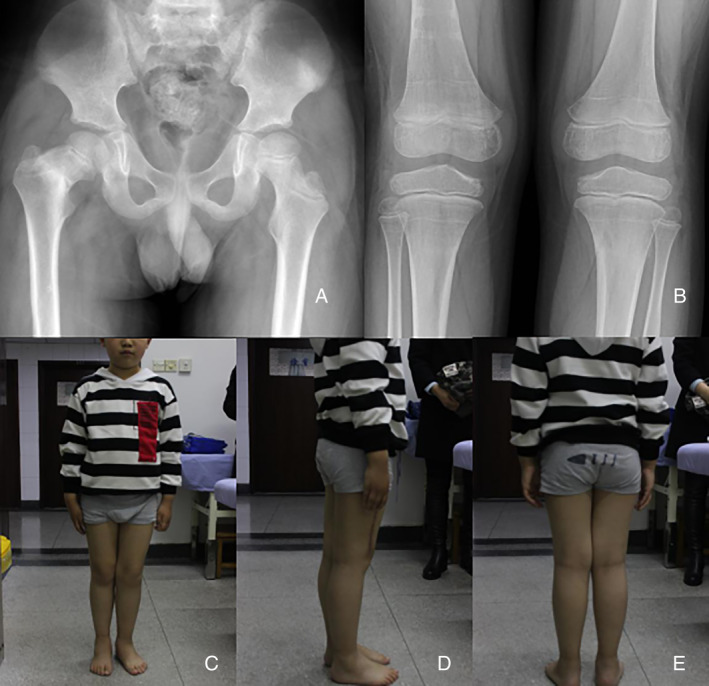

Figure 3.

(A) Thirty‐two weeks after conservative treatment, the right thigh neck shortening and internal rotation were found. (B) Twenty‐four weeks after bilateral proximal tibia fracture was found and conservative treatment, the right thigh neck fracture was continuous. (C,D,E) At the bilateral fracture site for 26 weeks. After 38 weeks of bilateral tibia fracture, the internal circumflex muscle of the right lower extremity atrophied slightly, and the shortening of the right lower extremity was not obvious.

After treatment, the deformity of the right lower extremity was basically corrected, and the shortening of the right lower extremity was not obvious (Fig. 3). After removing the external fixation, we examined the child in detail again: the child was 7 years and 5 months old, the body length was 134.1 cm, the weight was 36 kg, the total length of the right lower extremity was 69 cm, the length of the left lower extremity was 70 cm, there was no obvious tenderness pain, no obvious swelling, and right lower limb was slight varus. The trunk angle of the right thigh neck is about 122°. Other evaluations and results include percussion pain of the longitudinal axis of both lower extremities (−), pap sign (−), Patrick sign (+) of right lower extremity, normal muscle strength of the right lower extremity, no obvious abnormality in nervous system examination, temperature sense of extremities, touch sense, and superficial skin pain feeling. After fracture healing, the child had good exercise ability.